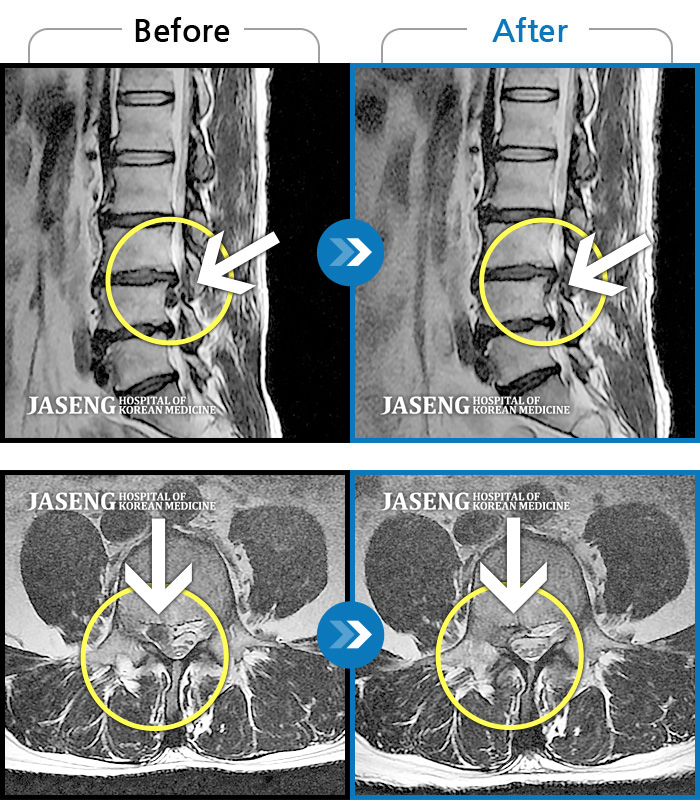

일산자생 한방 병원 한방진료팀 정승현 원장님과 담당 간호사분들께 감사드립니다. 지난해 11월 첫 병원 내원시에는 디스크가 터져서 허리와 다리통증이 심해서 의자에 앉기도 힘들 정도의 몸상태였습니다. 거리가 있어서 꾸준하게 통원치료 받는것이 힘들고 부담이 되었지만 늘 친절히 진료해주셔서 1차 3개월 치료를 받으니 어느정도 통증은 감소되었고, 2차 3개월 치료를 받고 MRI 사진으로 완치 판정을 받았습니다. 내원할때마다 차근히 상태 설명해주시고 치료해 주셔서 믿음을 가지고 꾸준히 치료받은 결과 전보다 보행도 더 편하고 허리상태도 정말 많이 좋아짐을 느낍니다. 원장님과 수고해주신 간호사님들께 다시한번 감사드립니다.